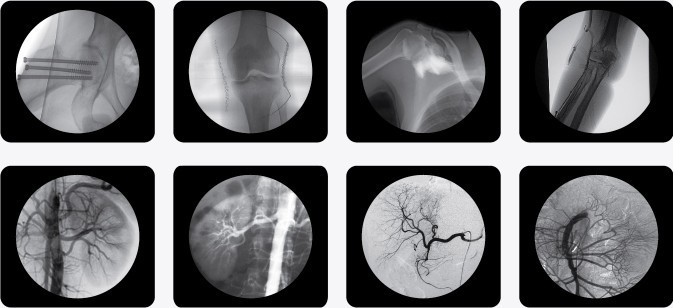

PLX7000B高頻移動式C型臂X射線機(C型臂X光機)

一、C型臂X光機PLX7000B的用途

廣泛應用于 介入科、骨科、外科、矯形外科、泌尿外科、脊柱外科、腹部外科、疼痛科、心臟科、消化科、婦科及手術室等。

二、C型臂X光機PLX7000B的特點

1、更大功率的高壓發(fā)生器適合對肥胖病人的高密度組織進行成像,更高熱容量的球館可以滿足長時間、大量手術的需要;

2、國內領先的全脈沖透視,智能曝光控制,實現(xiàn)超低輻射劑量

3、多種工作模式,滿足各種臨床需要

4、多葉與垂直光影控制,有效減少軟X線,大幅降低皮膚劑量

5進口品牌影像增強器,全數(shù)字化CCD攝像機,提供高分辨的優(yōu)質圖像。

6、高分辨率雙醫(yī)用液晶監(jiān)視器,大幅提高圖像效果

7、強大數(shù)字化圖文工作站標配DICOM3.0接口與網(wǎng)絡完美對接,支持Worklist登記和手動登記雙登記模式

8、工作站具有大容量數(shù)字化存儲功能,透視和數(shù)字點片均以數(shù)字化格式無損存儲,邊緣增強多重鏡像 gamma校正、電影回放、窗寬窗位、專家模板、刻錄等強大處理功能。

9、四維電動運動控制,定位精確,靈活自如;超大機架設計,提供了超大的診視空間,更加舒適的手術環(huán)境;全新設計,全新理念、帶來超凡體驗。

10、雙面板人體圖形化液晶觸摸屏,操作智能快捷;雙運動控制系統(tǒng)、雙曝光腳閘設計,極大滿足臨床操作。

三、C型臂X光機PLX7000B數(shù)字高清影像,支持您做出精確診斷

·數(shù)字化高頻發(fā)生器,采用微焦點,確保精準的射線劑量控制,滿足您的多種復雜臨床診治要求。

·球館大熱容設計,保證設備持久工作能力,伴隨您一同應對各種復雜手術。

·全數(shù)字化百萬像素影像采集系統(tǒng),優(yōu)化設計和配置,為您提供高分辨率、高灰階圖像,支持您做出精確診斷。

·專業(yè)的圖像處理系統(tǒng),具備非凡處理能力,確保您的所想即您的所得

1、內置先進圖像自動優(yōu)化處理、增強模塊,實時顯示自動優(yōu)化后的清晰臨床影像。

2、專業(yè)的影像處理工作站具備窗寬窗位調節(jié)、自動伽瑪校正、興趣點、反相、降噪、平滑、銳化等豐富且強大影像處理功能,帶給您更強大的診斷信心。

·專用高清醫(yī)用液晶顯示系統(tǒng),呈獻給您高亮度、高對比度的臨床圖像;對比自然,有益于診斷的圖像細節(jié)顯示更加清晰、層次更加豐富

四、C型臂X光機PLX7000B智能化數(shù)字脈沖劑量控制技術,全力降低射線危害,呵護醫(yī)患健康

·自主開發(fā)掌握了國內領先的數(shù)字脈沖劑量智能控制技術,在保證清晰影像的同時,大幅降低射線對醫(yī)患輻射的危害,達到歐盟醫(yī)療器械相關要求

·多葉與垂直(可旋轉)光野控制,有效減少軟射線

·紅光十字定位功能,協(xié)調操作者在術前準確定位檢查點,減少不必要曝光

·當您需要遠離射線源以避免輻射傷害時,我們提供專業(yè)的遠程曝光控制系統(tǒng)

·專業(yè)數(shù)字化影像工作站具備靜止圖像、動態(tài)影像存儲、回放功能,有效減少重要曝光。